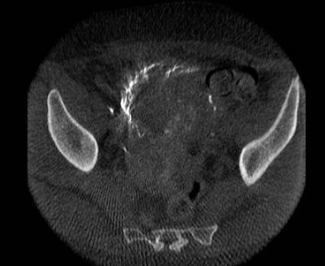

所有年龄超过 40 岁的患者, 卵巢受损 14%-43% 研究中闭经发生率(15%)与单纯UAE报告相似,可能与患者年龄(≥45岁)及卵巢储备自然下降有关。 ![]() 50岁,长期因子宫肌瘤导致月经出血过多,痛经和贫血。 子宫肌瘤栓塞术前,显示双侧子宫动脉发育不全,子宫肌瘤双侧卵巢动脉。 经皮股动脉穿刺双侧卵巢动脉栓塞,先500μm-700μm emboSphere 微球 术后4周,和6月的中短期随访,月经正常,子宫容积减少,贫血纠正,无卵巢功能衰竭。但看起来非灌注容积较少。 术后9月,由于子宫肌瘤持续存在,患者自己希望绝经,行全子宫和双侧卵巢切除术 术后病理,子宫内可见栓塞微粒伴有坏死,卵巢内也见栓塞微粒,但卵巢功能未受损。